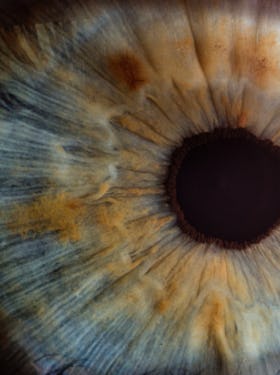

Avec plus de 20 ans d’expérience, nos ophtalmologistes chirurgicaux et expérimentés ainsi que toute l’équipe vous accueilleront et prendront en charge vos troubles réfractifs dans une atmosphère conviviale dotée d’une Technologie ultra-moderne.

Le centre laser BELLE ÉTOILE met tout en œuvre pour vous garantir le meilleur résultat visuel dans des conditions uniques de modernité, de confort, d’asepsie et de sécurité exemplaire.